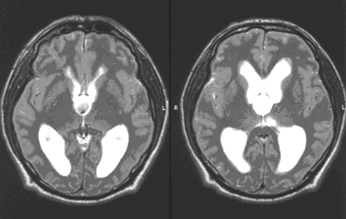

Оптимальный метод диагностики — МРТ, выявляющая округлой формы образование по средней линии в передних отделах III желудочка (рис. 1).

Рисунок 1. МР-томография больного с коллоидной кистой III желудочка, выраженной гидроцефалией (в режиме Т2, аксиальный срез)